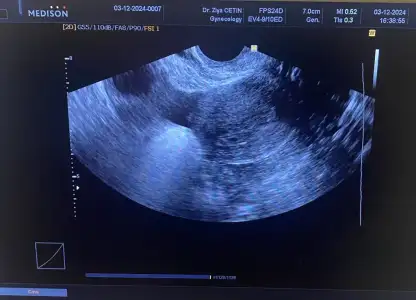

Süper kuzum maşallahSelamlar bene bugün ilk doktor kontrolüme gittim. Vajinal olarak keseye baktık ve gördük şükür tek gebelik dedi5+1, 2 hafta sonra gel kalp atışına bakalım dedi bakalım nasip

Selamlar bene bugün ilk doktor kontrolüme gittim. Vajinal olarak keseye baktık ve gördük şükür tek gebelik dedi5+1, 2 hafta sonra gel kalp atışına bakalım dedi bakalım nasip

Canım karından bakıp göremeyince mi vajinal baktı hekim?Selamlar bene bugün ilk doktor kontrolüme gittim. Vajinal olarak keseye baktık ve gördük şükür tek gebelik dedi5+1, 2 hafta sonra gel kalp atışına bakalım dedi bakalım nasip